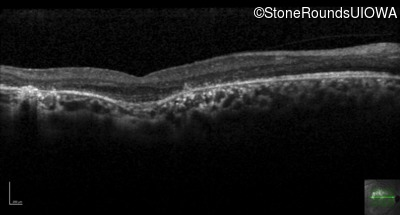

Optical Coherence Tomography - Left - 20/20 -3

Exemplar / OCT Stack

OCT Stack